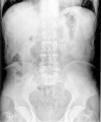

Caso 2Varón de 68 años, colecistectomizado y con una gastroenteroanastomosis tipo Billroth II realizada 20 años antes por un ulcus péptico, con la boca anastomótica permeable en un control endoscópico 3 años antes. Acudió a urgencias por dolor abdominal irradiado a zona lumbar izquierda de 3 días de evolución, acompañado de náuseas, vómitos posprandiales, diarrea sin productos patológicos y anorexia con pérdida de 3-4 kg de peso en el último mes. Refería dispepsia habitual con pirosis y saciedad precoz, que trataba con omeprazol y almagato. En la exploración física el abdomen era blando pero doloroso a la palpación. En una radiografía simple de abdomen se observó un patrón en miga de pan distribuido por el cuadrante superior izquierdo (fig. 1) y en la TC se observó una dilatación gástrica con abundante retención alimentaria sólida compatible con un fitobezoar. Se colocó una SNG en aspiración y se inició tratamiento con metoclopramida i.v. 10 mg cada 6 h y celulasa 5 g al día durante 5 días administrada de la misma forma que en el caso 1. Una EDA realizada a las 24 h de finalizar el tratamiento mostró restos vegetales que formaban una masa de 4 cm de diámetro y de consistencia media, que para eliminarla se fragmentó mediante asa de polipectomía. Tras comprobar ausencia de restos de fitobezoar mediante radiología (fig. 2) se reintrodujo la dieta oral sin complicaciones y se dio el alta a las 48 h de finalizar el tratamiento.